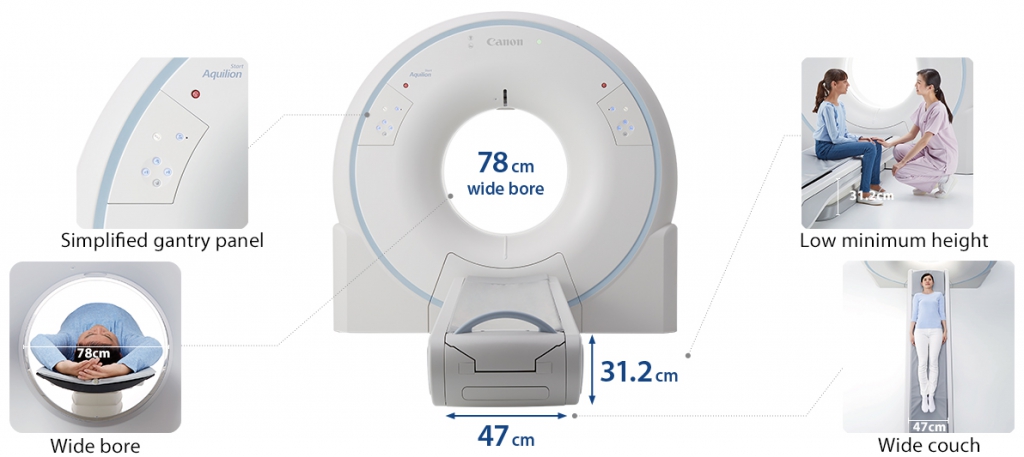

Новый, улучшенный гентри — упакован по технологии

Гентри Aquilion Start включает в себя инновационные разработки, которые улучшают качество сканирования пациентов и обеспечивают отличную работоспособность и безопасность.

Просторное отверстие шириной 78 см и кушетка шириной 47 см позволяют комфортно сканировать даже самых крупных пациентов. Кушетка может быть опущена до минимальной высоты 31,2 см, что облегчает перенос пациентов с инвалидной коляски.

Простота эксплуатации:

- Сканирования одним нажатием

- Возвращение на исходную позицию в один клик

- Снижение требований к обучению

Качественный уход за пациентами и операторами:

- Самый низкий стол в отрасли

- Более легкое перемещение с инвалидной коляски

- Минимизирует напряжение движений пациентов